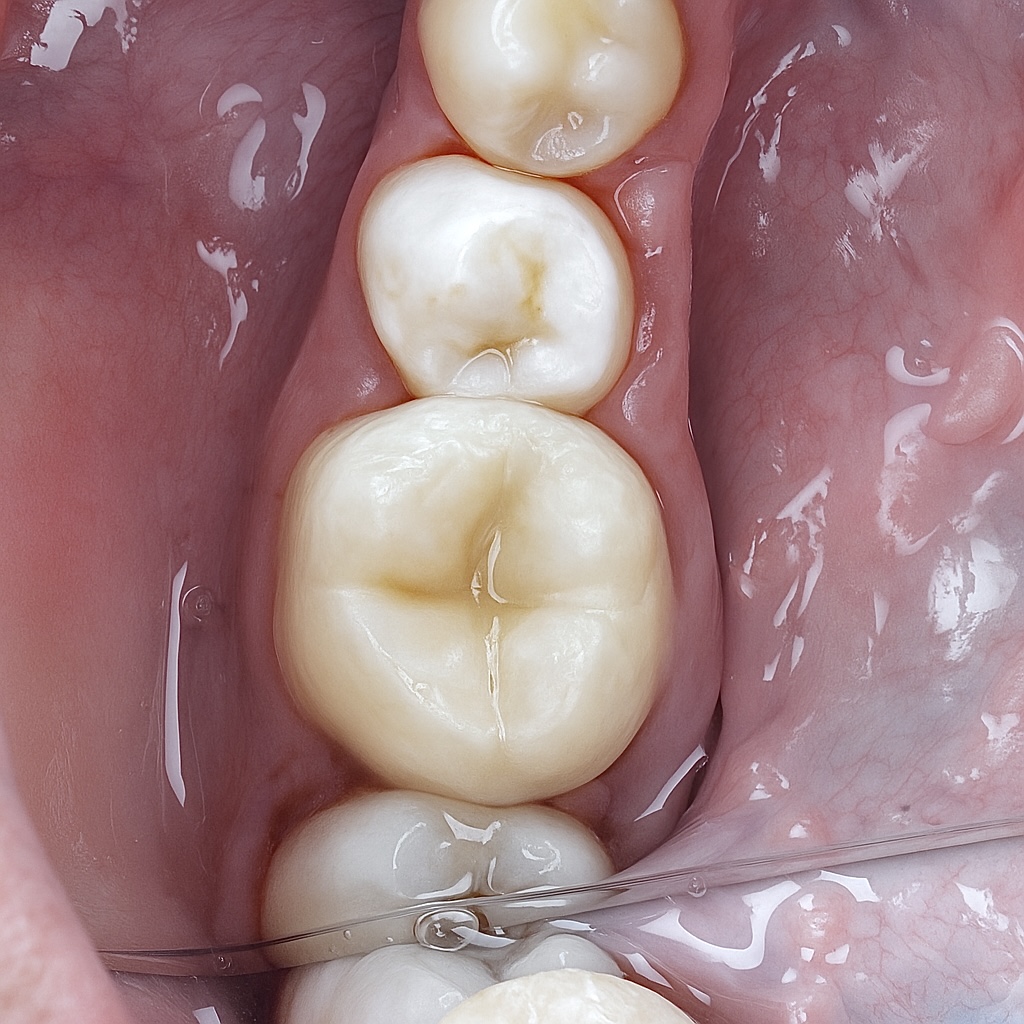

6. Final Outcome

- Clean radiographs with excellent obturation length and density

- Proper coronal seal with fiber reinforcement

- Natural occlusal anatomy matching adjacent teeth

- Smooth, glossy, gingiva-friendly margins

- Full function restored with long-term structural integrity